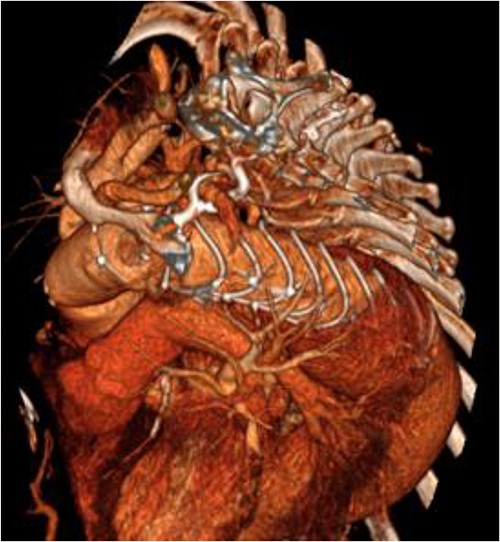

An 8 mm Gelweave graft was anastomosed to the left subclavian artery. Standard cannulation technique was used with the distal aorta and the right atrium. The distal aorta was sized and a 30/32 mm (15 cm length) Thoraflex graft was anastomosed with 4–0 prolene and reinforced with 1.5 cm Teflon. The supra-aortic vessels were reimplanted separately; deep hypothermia (20°C) was utilized for neuroprotection with antegrade cerebral perfusion and near infrared spectroscopy monitoring. Proximal aorta anastomosis followed patient rewarming. Her post-op CT aorta showed adequate perfusion and FET placement. A 3D reconstruction is shown in Figs 2 and 3. She was discharged on Day 10 and successful TEVAR was undertaken 8 months later (Fig. 4). Follow-up 24 months later showed no evidence of endoleak, stent migration or fracture.

3D reconstructed CT aorta image showing successful FET implantation at zone 0.